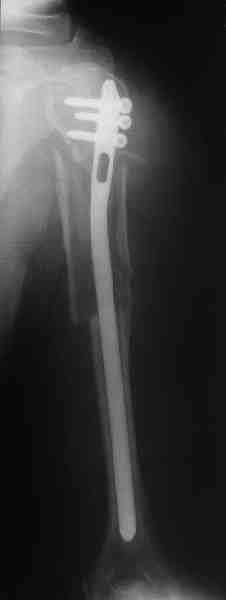

Прооперировали больную с переломом плеча все же гвоздем, Фото в приложении.

Гвоздь большеберцовый нашей модификации, действительно, их делает предпричятие "ЦИТО". Тут взят 9 мм, укорочен до 240 мм, сделано дополнительное отверстие самое проксимальное, ну и для дистального винта.